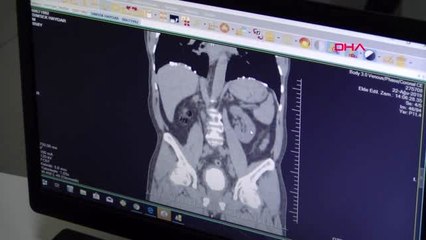

Mesanesinden 522 gramlık tek parça taş çıktı